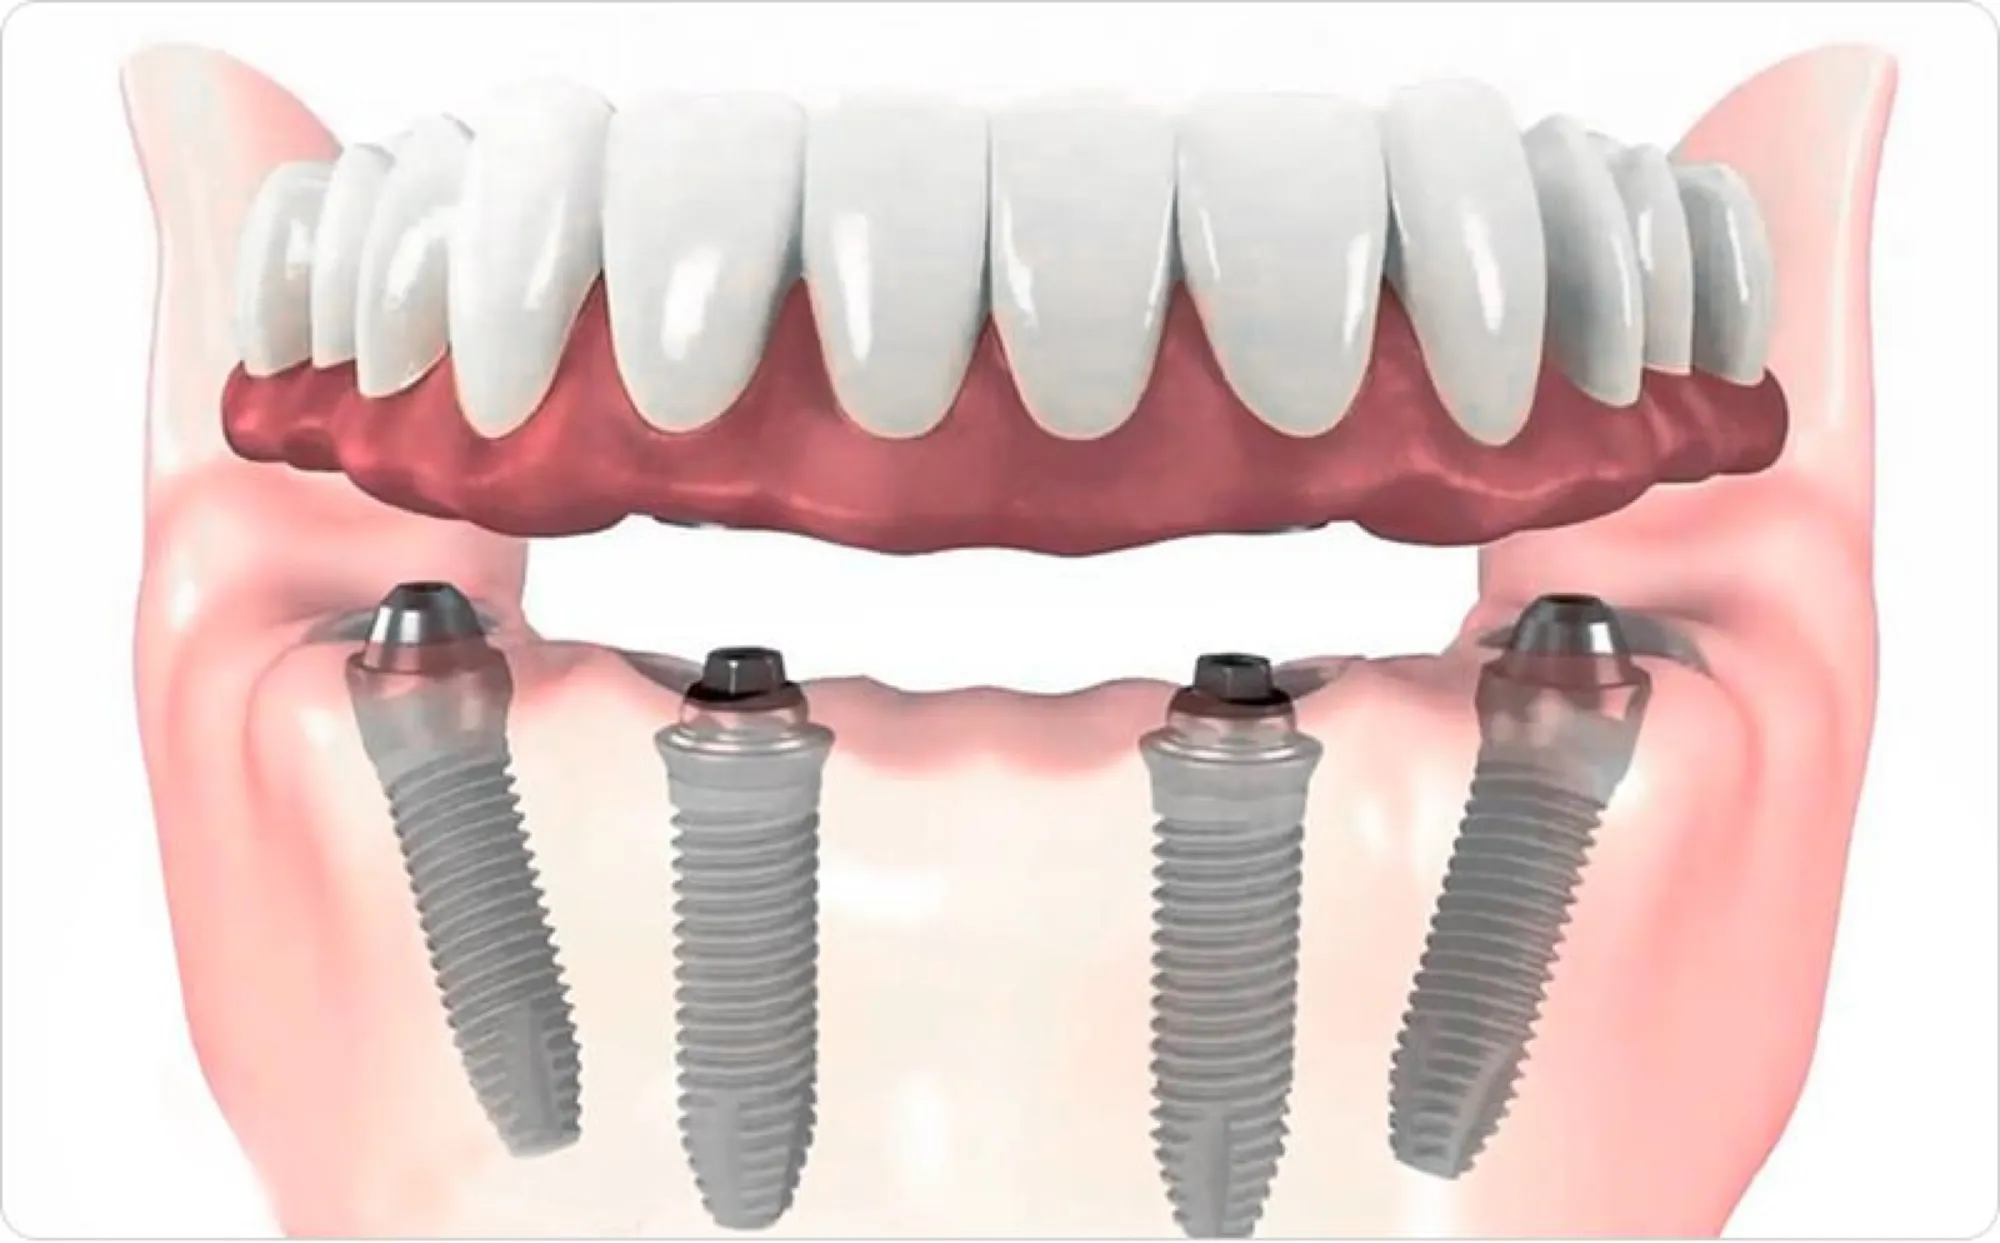

Технология All-on-4 разработана для реабилитации пациентов, страдающих полной или почти полной адентией в жевательных отделах челюсти и атрофией костной ткани. Основная концепция заключается в установке четырех дентальных имплантатов, располагаемых таким образом: два в передней части и два под углом от 25 до 45 градусов в задней части челюсти. Непосредственно после этой процедуры производится немедленное протезирование зубов несъемным протезом.

Угловая установка имплантатов в этом методе позволяет использовать имеющийся объем кости без необходимости наращивания костной ткани. Это предотвращает болезненные процедуры наращивания кости и значительно сокращает общее время лечения.

В рамках одного визита удаляются поврежденные зубы, вживляются четыре имплантата, устанавливаются абатменты. После этого делаются слепки для временного протезирования, который изготавливается и устанавливается в тот же день, обычно через несколько часов после операции.